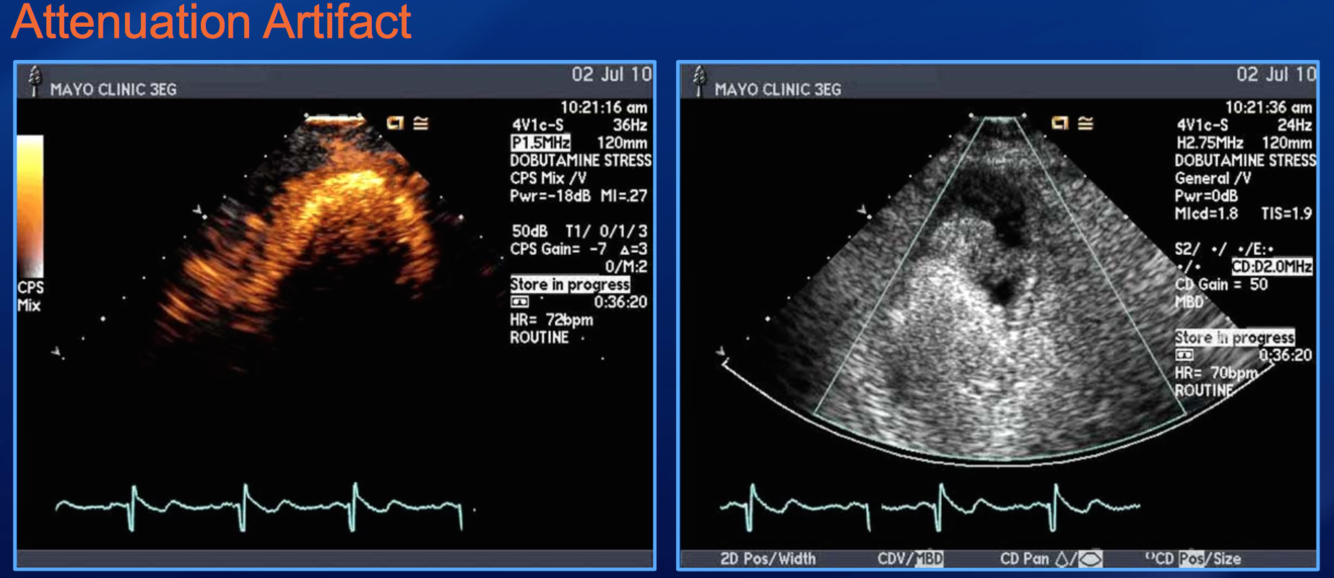

if you see contrast light up LV apex with ATTENUATION of rest of LV, what to do?

transiently inc MI and inject contrast softer and slower

what do you do when you see this?

INCREASE M.I., push slower/less